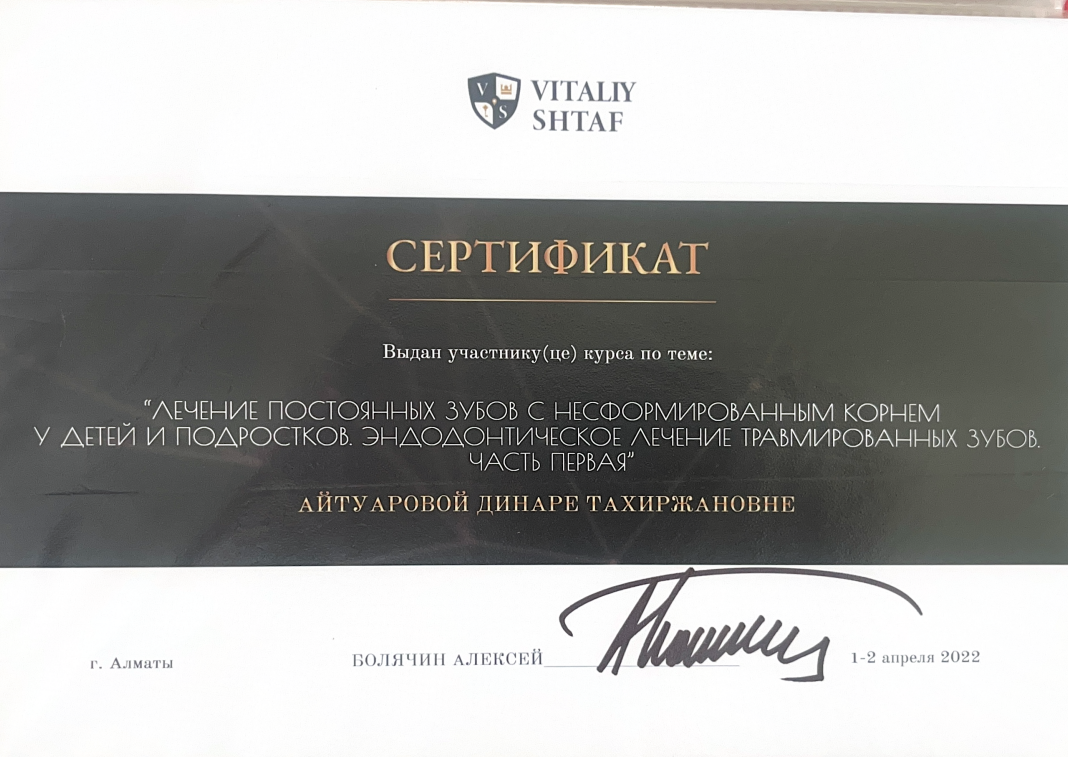

Айтуарова Динара Тахиржановна

Практикующий врач-стоматолог с более чем 23-летним стажем.

Обучается новым технологиям и внедряет современные методы в практику